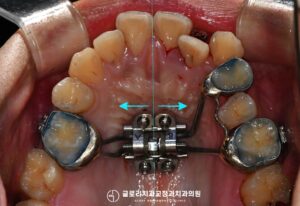

망우동 치과 정중선 편위 및 삐뚤어진 치열, 가지런한 배열을 회복하기 위한 발치 교정

안녕하세요 망우동 치과 김정은 원장입니다. 치아가 삐뚤어 교정 상담을 받게 되면 많은 분들이먼저 궁금해하시는 것이 바로 비발치 인지 발치 교정인지에 대한 부분입니다. 23.07.18 가능하다면 치아를 뽑지않고 배열만 정리하는 비발치 방식을…